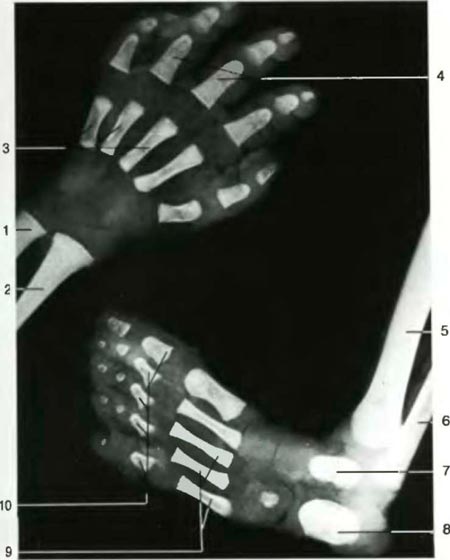

1. Локтевая кость 2. Лучевая кость 3. Пястные кости 4. Фаланги пальцев 5. Большеберцовая кость 6. Малоберцовая кость 7. Таранная кость 8. Пяточная кость 9. Плюсневые кости 10. Фаланги пальцев 1. Ulna 2. Radius 3. Ossa metacarpi 4. Ossa digitorum - phalanges proxima 5. Tibia 6. Fibula 7. Talus 8. Calcaneus 9. Ossa metatarsi 10. Ossa digitorum-phalanges proximales-stopy |

1. Лопатка